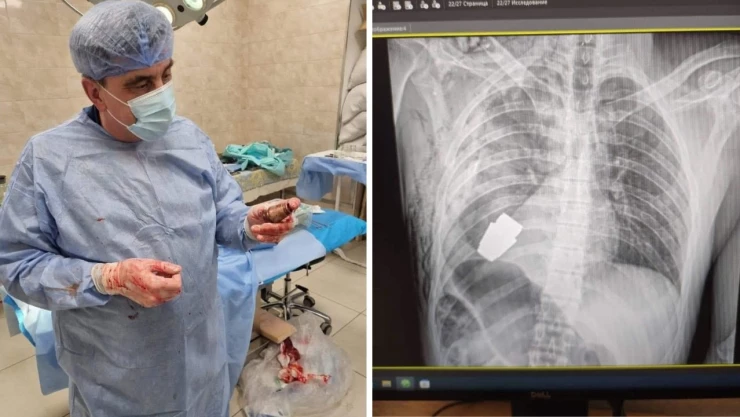

La viceministra de Defensa de Ucrania, Hanna Maliar, difundió algunas fotografías de la radiografía del soldado con la granada incrustada en el pecho y después otra donde aparece uno de los cirujanos con el explosivo en la mano.

“Nuestros médicos militares realizaron una operación para extraer una granada sin explotar del cuerpo de un soldado. Uno de ellos, el más experimentado de las Fuerzas Armadas, el mayor general Andriy Verba, trabajó sin electrocoagulación, ya que la granada podía detonar en cualquier momento”, explicó Serhii Borzov, el gobernador regional en un breve comunicado compartido por Telegram.

Después de la cirugía, el soldado ucraniano fue enviado a rehabilitación donde se espera su completa recuperación. Los médicos indicaron que, aunque la granada no explotó al momento de la cirugía, sigue siendo explosiva”.